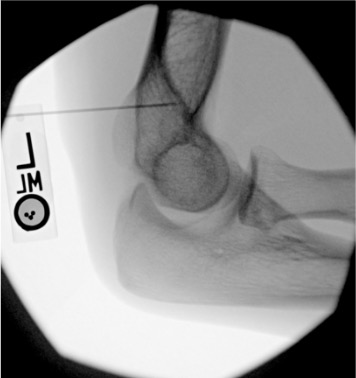

| Elbow | 3–5 mL | Fluoroscopy or ultrasound | Lateral (radiohumeral) approach | Triangle formed by lateral epicondyle, radial head, and capitellum; elbow flexed 90°; posterior fat pad elevation on lateral radiograph suggests intra-articular effusion and facilitates access |

Elbow

Needle placementPost-injection